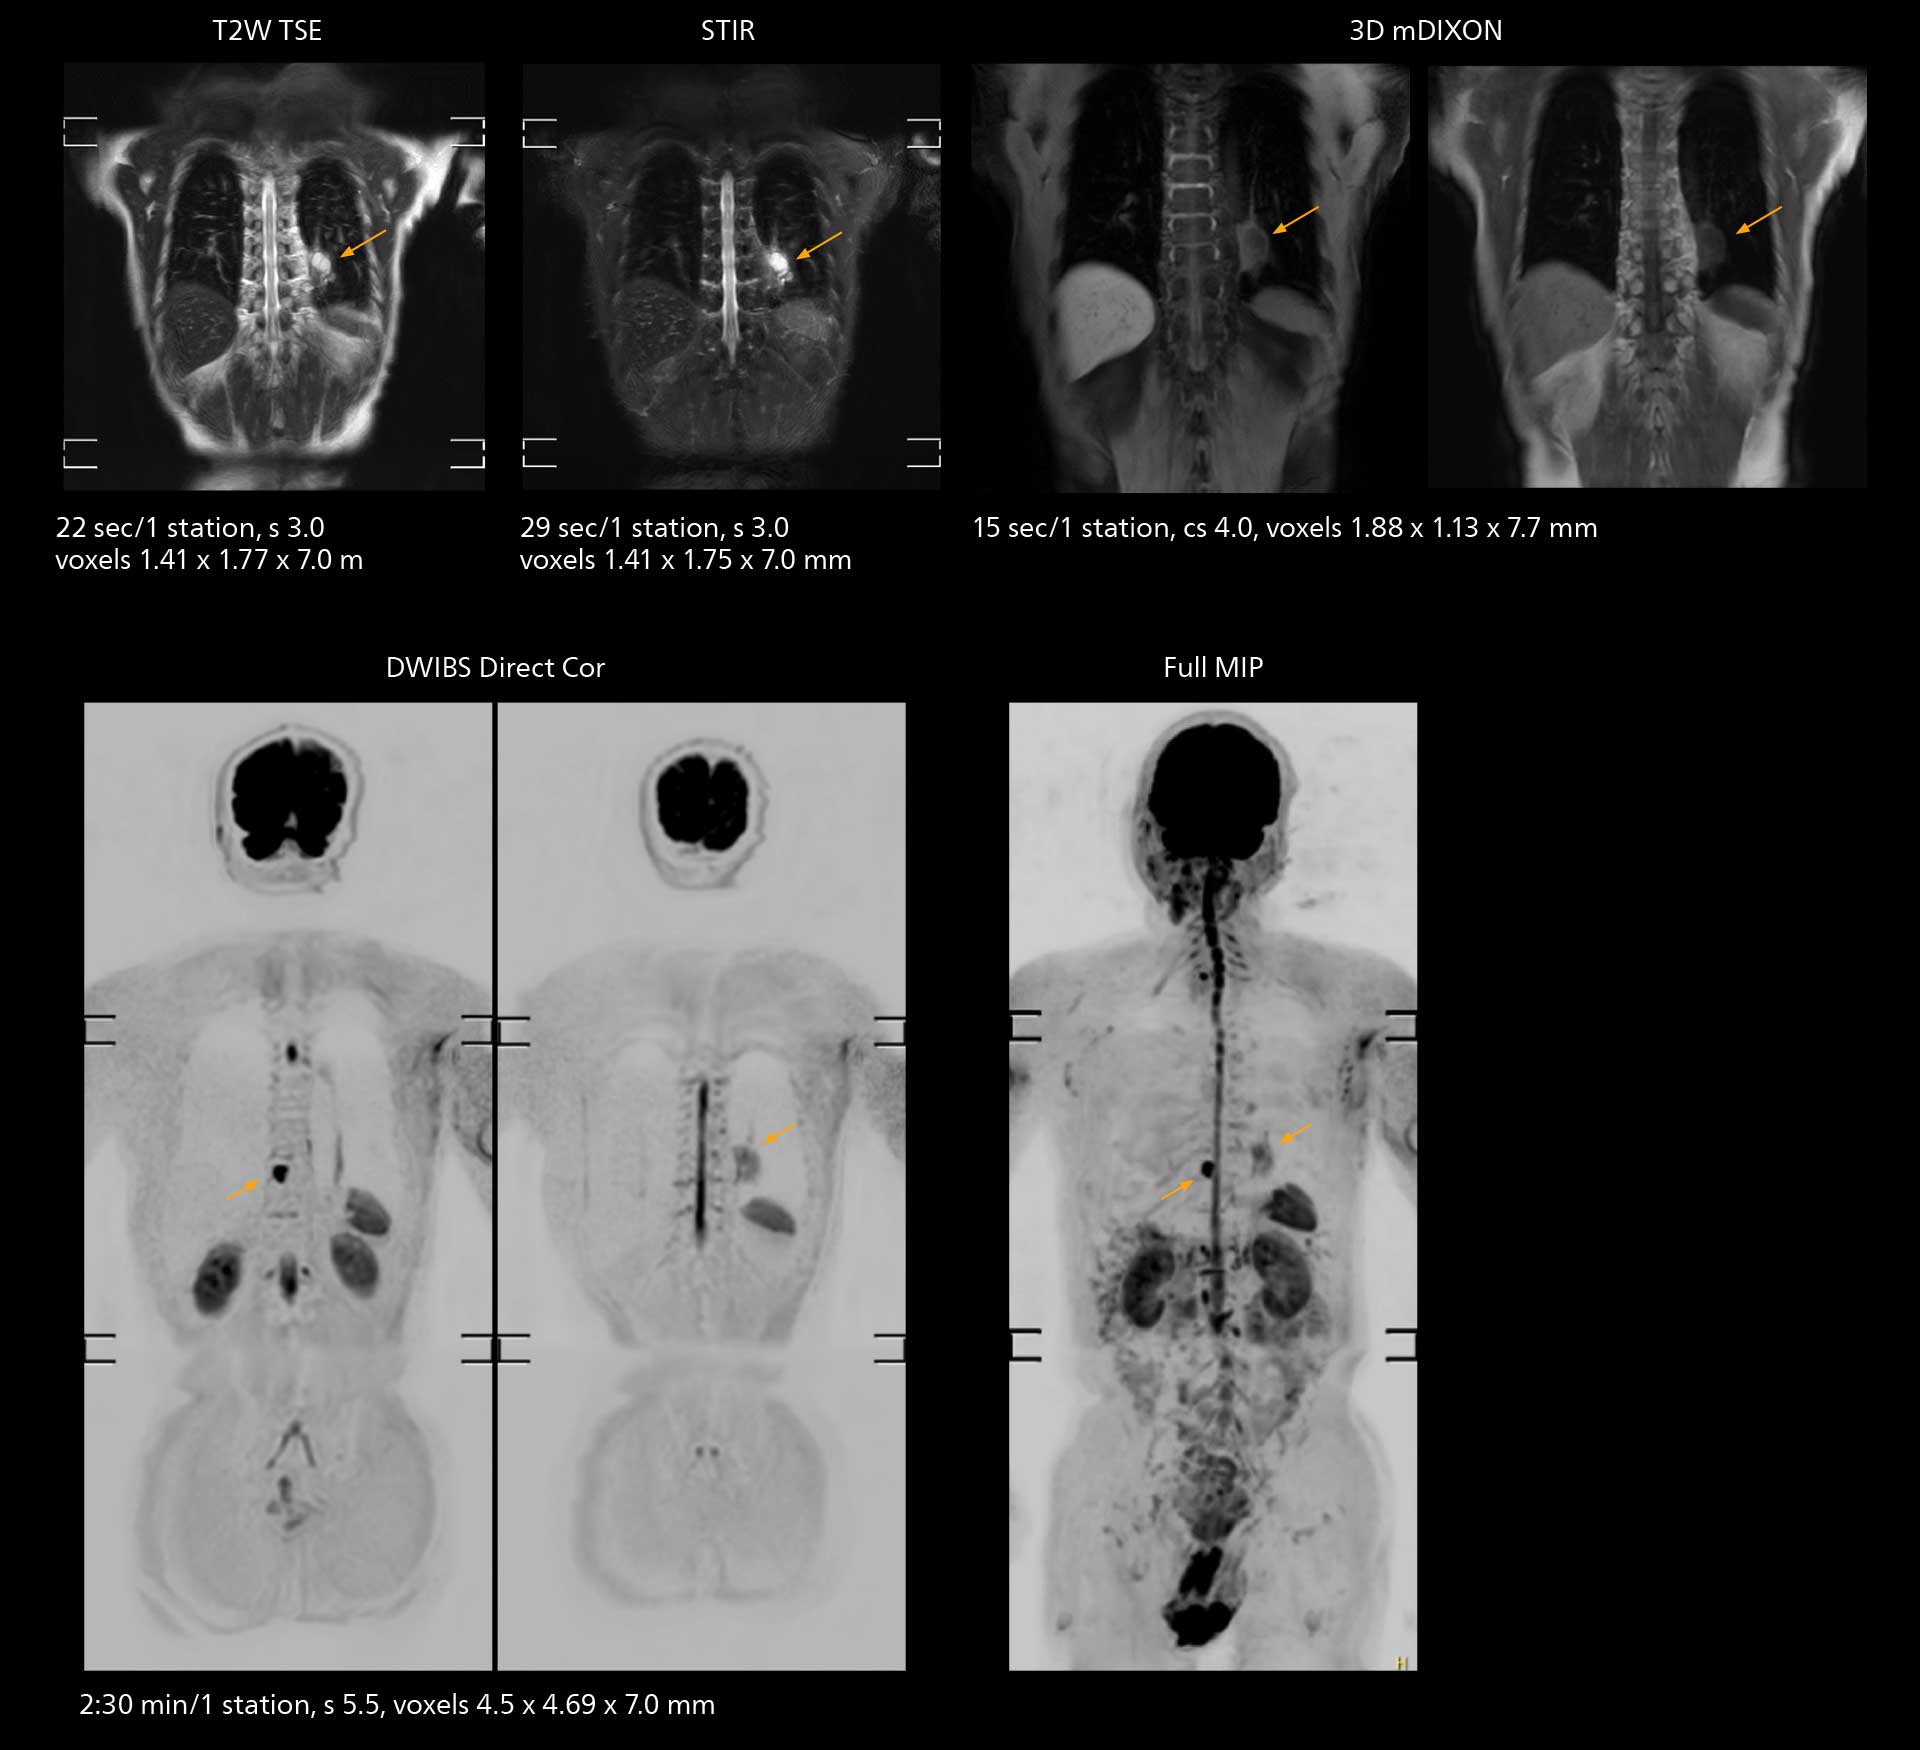

The value of the Elition X gradients is also evident in DWIBS studies. “The fact that we can consistently obtain distortion‐free DWIBS while reducing imaging time at three coronal stations is excellent,” Dr. Makuuchi says. “In these patients, it’s also important that the application of Compressed SENSE to T2‐weighted, STIR and mDIXON sequences has no impact on the examination time of whole‐body imaging. As a result of the increased speed and higher image quality we realize, DWIBS studies have now become routine examinations.”

Fast whole body DWIBS examination

With SmartPath to Elition X the team can obtain excellent quality DWIBS imaging and reduce imaging time. Other sequences also fit in the examination slot. This case shows left paravertebral neurogenic tumor and Th10 vertebral hemangiomas.